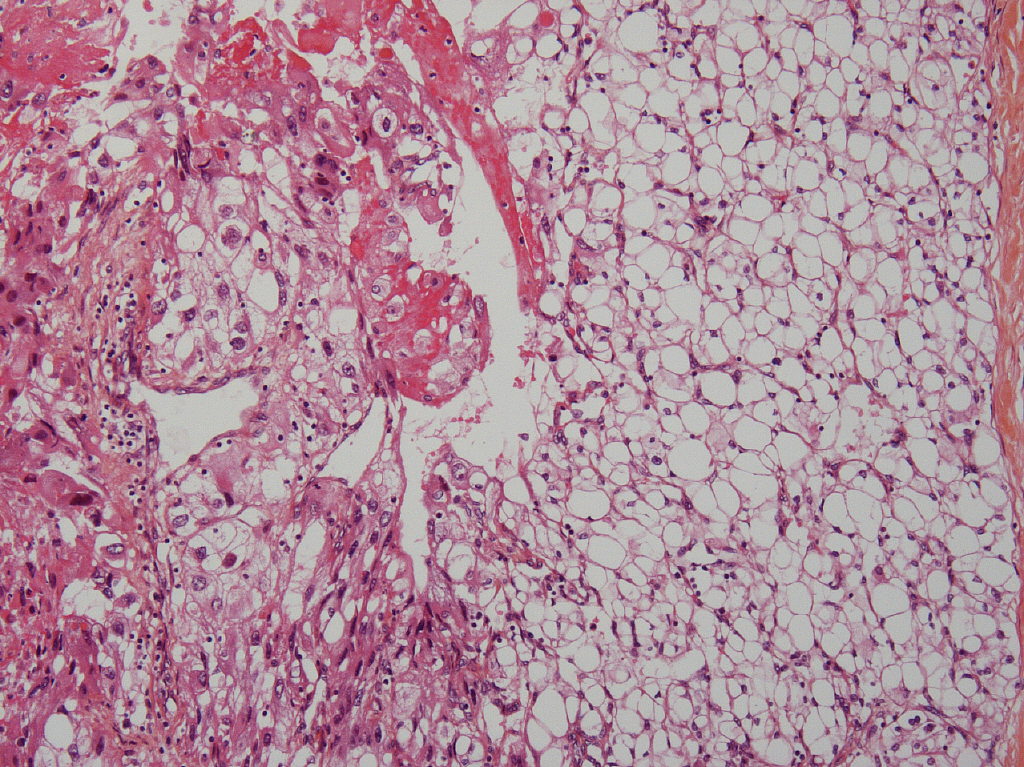

Consensus grade: WHO/ISUP grade 3

Clear cell carcinoma with different grades